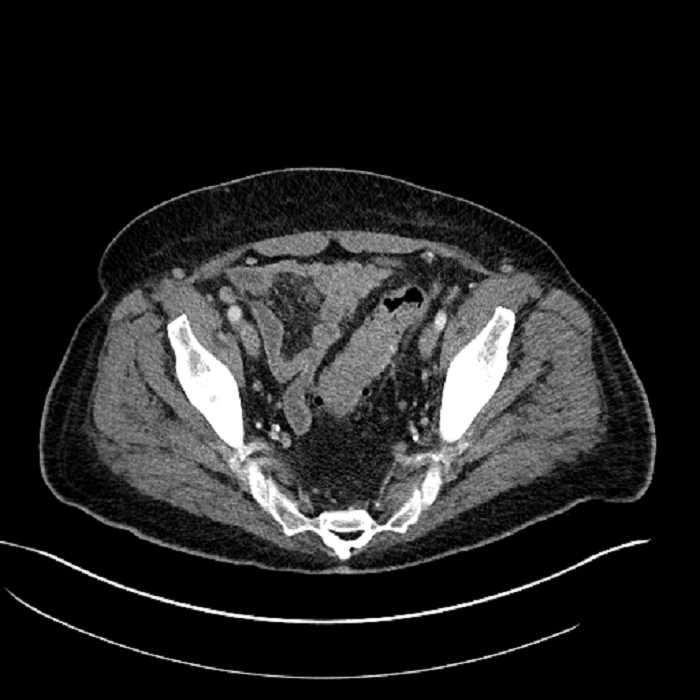

Age: 63

Sex: Male

Indication: Abdominal pain

• High grade stenosis of the left common iliac artery, with the left internal and external iliac arteries remaining patent

• Ankylosis of both sacroiliac joints

Acute sigmoid diverticulitis complicated by a small contained perforation and a large abscess in the right hepatic lobe. Additional small subcapsular abscesses along the anterior margin of the left hepatic lobe.

High grade stenosis of the left common iliac artery. The left external and internal iliac arteries are patent.

Hepatic abscess showing the double target sign with low density internally surrounded by a thin inner enhancing rim (red arrow) and ill-defined outer low density rim (yellow arrow). Blue arrow indicates an internal septation. Red arrows: additional smaller subcapsular abscesses. Red arrow: focal contained perforation associated with diverticulitis.